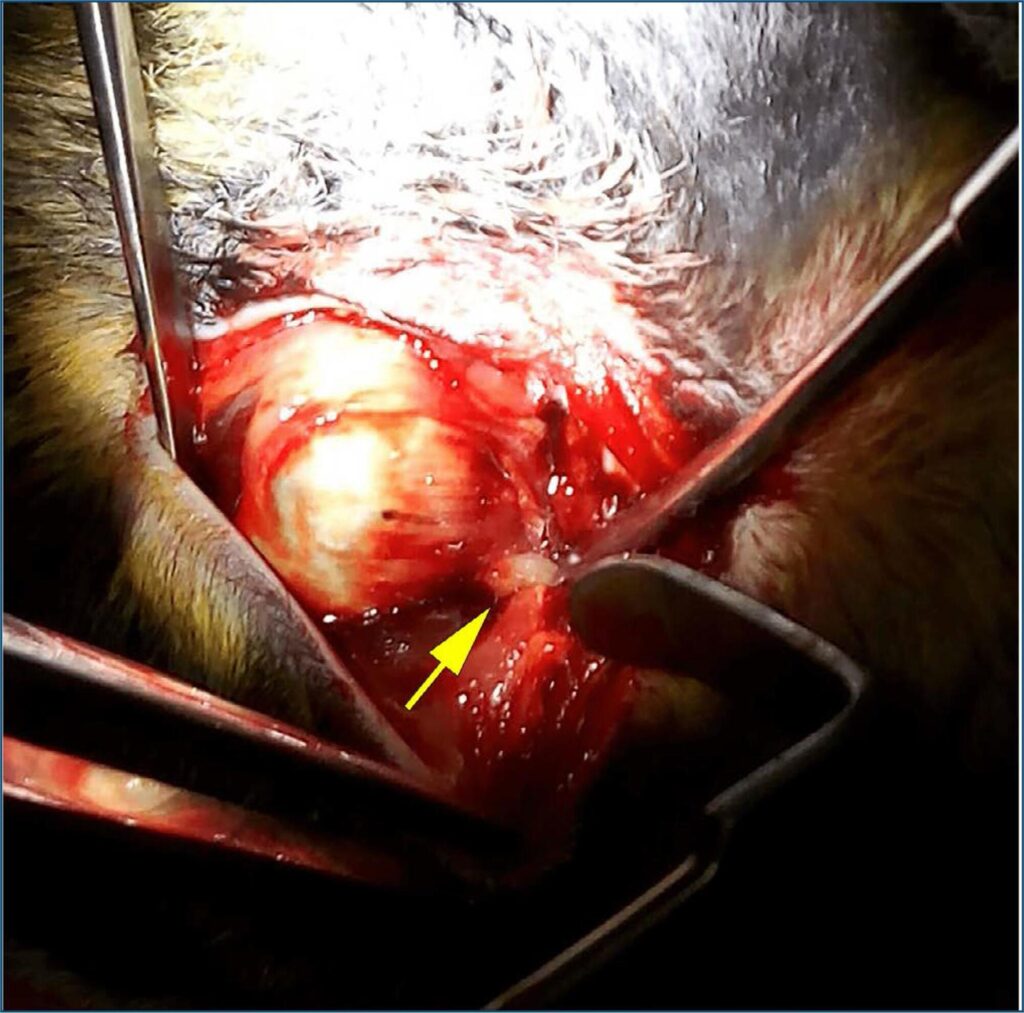

Descrever uma técnica cirúrgica inovadora para transplante de olho em um modelo animal em coelhos.

Seis coelhos machos com Dutch Belted foram submetidos à orbitotomia lateral do olho direito, com ampla exposição da anatomia retrobulbar, dissecção do cone muscular, exposição e secção distal do nervo óptico seguida de anastomose por vicryl (Grupo 1) ou cola de fibrina (Grupo 2). O registro da eletrorretinografia foi realizado antes da secção do nervo óptico e a cada 30 segundos após, para monitorar a função da retina. O olho esquerdo foi usado como grupo controle.

O modelo animal de transplante total de olho foi eficaz em descrever uma nova técnica cirúrgica para ser utilizada em laboratório com coelhos, com sucesso do procedimento anatômico. Novos estudos esclarecerão os melhores métodos de anastomose e manutenção da função do órgão receptor.